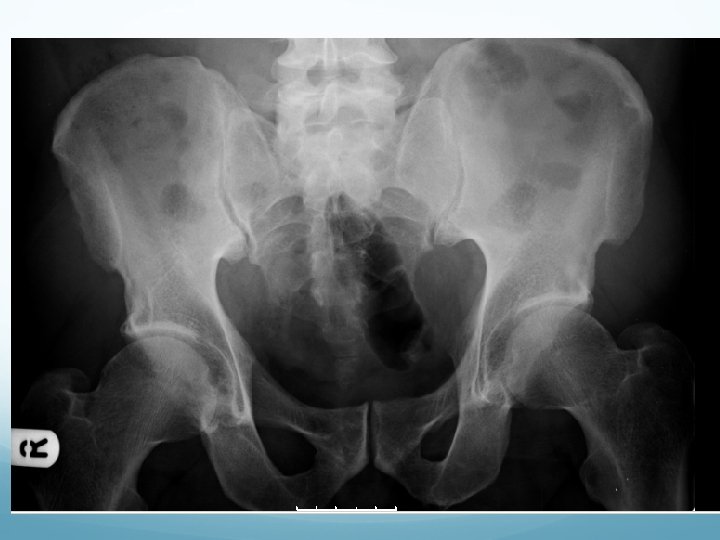

What to look for on a KUB � 90% stones are radio-opaque � Ureteric stones are sausage shaped due to peristalsis of ureters 1. Outline of kidneys 2. Path of ureters � Hila of kidneys L 1 � Tips of transverse processes � SIJ at pelvis 3. Sites of impaction � PUJ � Pelvic Brim � VUJ 4. Rest of abdominal film

1. Outline of kidneys 1. Path of ureters 1. Sites of impaction 1. Rest of abdominal film

What to look for on an IVU � ALWAYS look at KUB first � CT KUB is gold standard, and only option if U+Es are abnormal 1. Nephrogram � � Contrast in kidney Persistent increasingly dense nephrogram in obstruction 2. Pyelogram � Calyces: � � � ? clubbed / more prominent Extravasation of contrast Ureters: � � � Peristalsis: Normal Dilatation Standing column